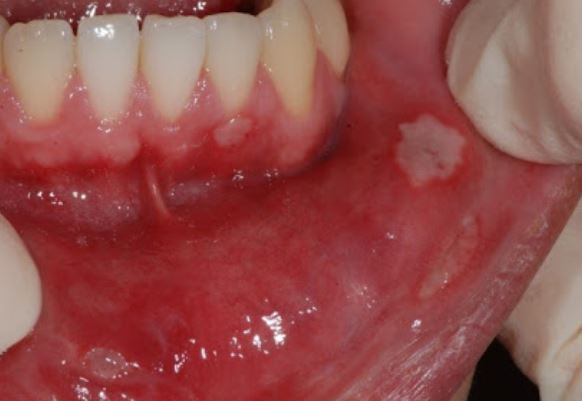

하 얼마 전 밥을 먹다가 볼따구 안쪽을 씹어버렸어요. 처음에는 씹은 부위만 살짝 아픈 정도? 피가 살짝 나는 정도였는데, 얘가 점점 구내염으로 발전하더라구요.

내가 이럴 줄 알았지...때론 술을 며칠 내내 마시면 생기기도 하고, 때론 잠을 잘 못잘 때 생기기도 하는 구내염. 대부분의 분들은 피로나 스트레스때문에 생기는 아프타성 구내염이 생깁니다. 이름부터 아파보여

흔히들 이렇게 말하죠. '너 입안에 흰거 났다' 그 흰거가 아프타성 구내염입니다. 진짜 짧으면 5일, 길면 2주간 아파가지고 밥먹을 때 혹은 음료수를 마실 때마다 통증을 줍니다.